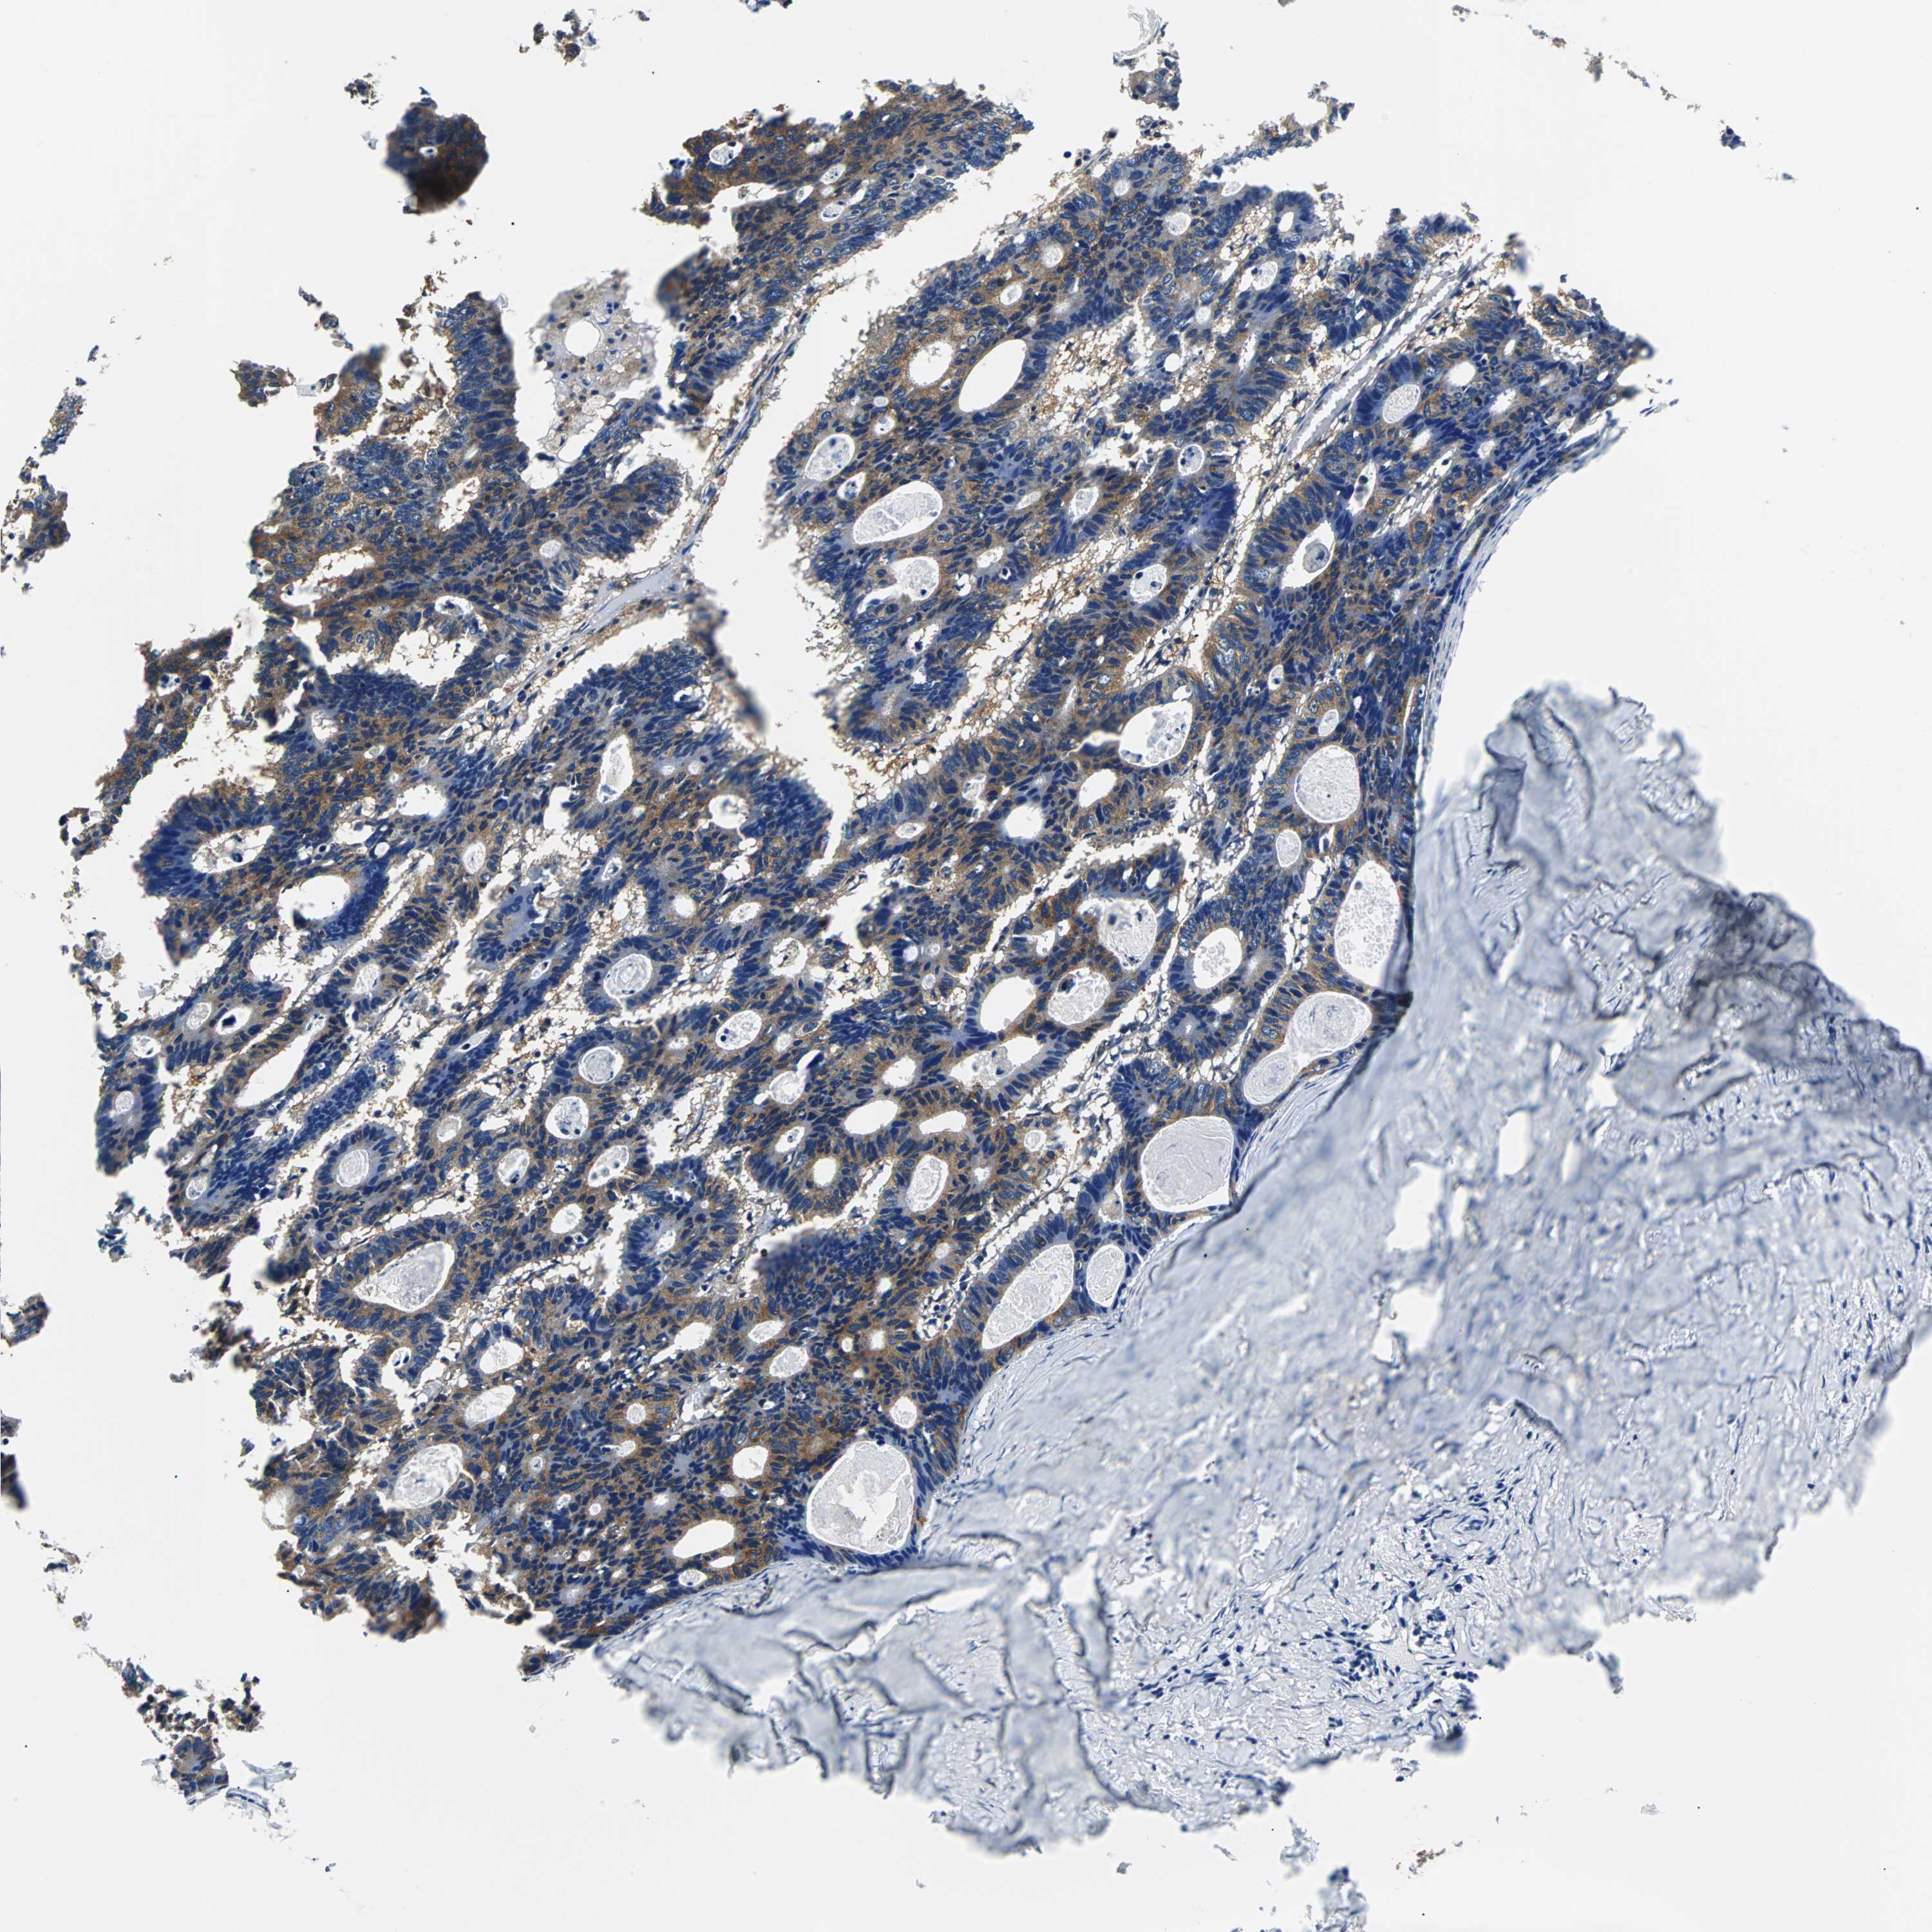

CANCER COLORECTAL CANCER Show tissue menu

Colorectal cancer

Human cancer

Colon adenocarcinoma